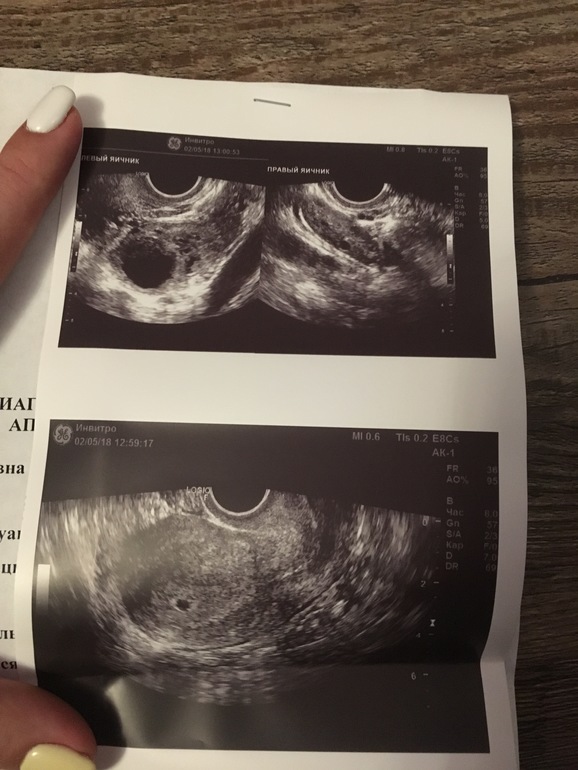

Результат УЗИ

06.05.2018